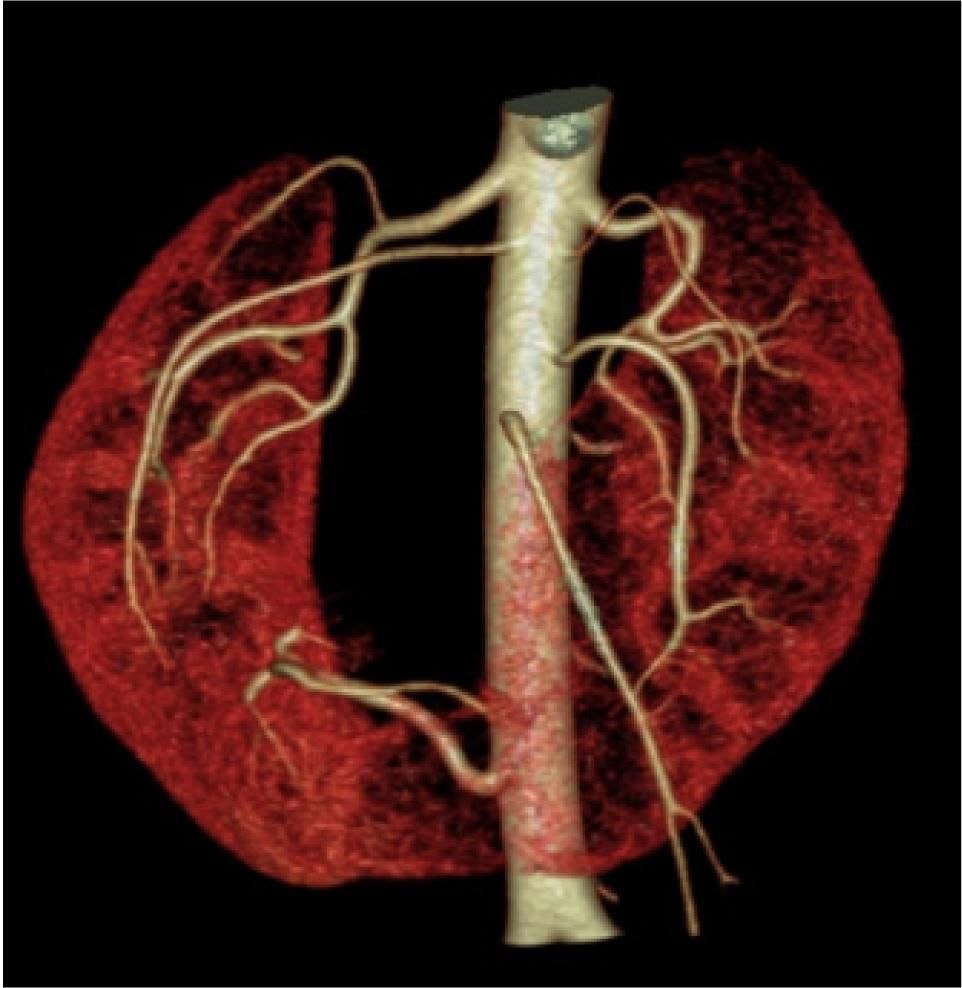

Furthermore, the patient was subjected to CT renal angiography which revealed one main renal artery showing hilar branching supplying right upper and interpolar region, and right accessory renal artery supplying interpolar and lower polar region. Left main renal artery showed hilar branching supplying the left interpolar and lower polar region. Out of the two left renal accessory arteries, one artery supplied the left interpolar and lower polar region and the other artery supplied the left upper pole. Another artery arising from infra renal abdominal aorta on the right side at the level of third lumbar vertebra trifurcated the medial branch that supplied isthmus, middle branch that supplied tumor, and lateral branch that supplied the right kidney (Figure 5). Patient could not afford PET-CT, and TNM staging revealed PT1bN0M0 Stage 1.

Figure 5: Three-dimensional volume rendering CT angiography showing renal and accessory arteries on either sides supplying both kidneys. Another artery arising from infra renal aorta supplying isthmus, tumor, and adjoining lower pole of right kidney.